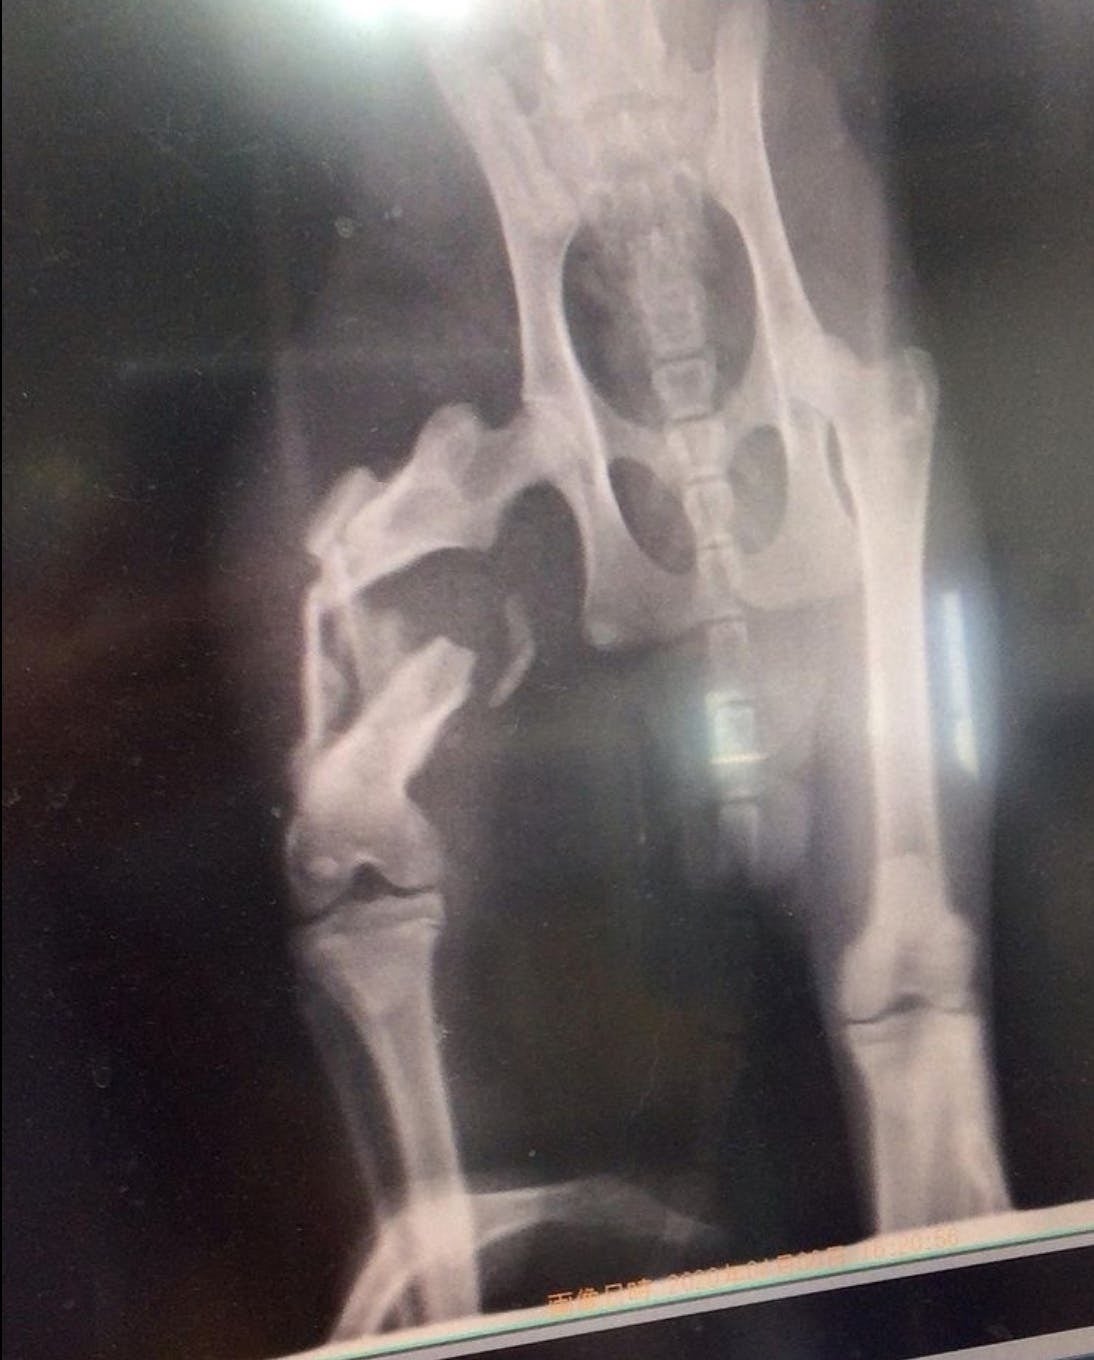

一朗くん

福岡県で足を引きずっている猫を発見し、その辺りの方に聞いたところ、

偶然にもそこでご飯をもらっていました。

その人が言うには、野良猫でご飯をあげていたが、車に轢かれ2週間ほど姿を消していたので、

死んだかなと思っていたそうです。そしたら、最近になってふらっと姿を見せたそうです。

人間が事故にあったら皆んな助けてくれるのに、猫の場合はほったらかしですか?

一人で2週間もの間 痛みに耐えていたんだね…

こんな辛い思いをした子を、放ったらかしにして帰ることが出来ず、保護させてくださいとお願いしました。

今では、本当に骨折してたの??と思うくらい走り回っています。